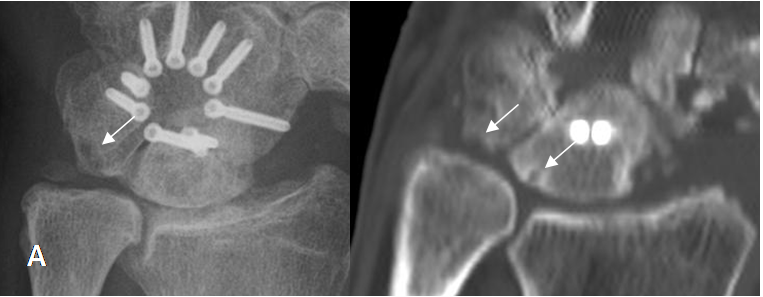

Fig 83. Impactación ulnar.

A: Rx AP. Varianza ulnar positiva, con erosión del piramidal. Adicionalmente hay fijación de los huesos del carpo, con ausencia del escafoides.

B: TAC reconstrucción coronal. Varianza ulnar positiva, con erosión del semilunar y piramidal.